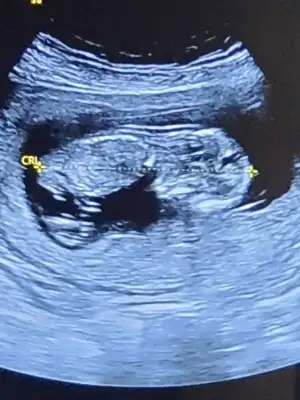

dr soylemeden siz gorun genital nub teorisi ( bebegin cinsiyeti)

Lütfen bana da tahminde bulunun cok merak ediyorum 🤩🤩

Eklentiler

• IMG_20201210_132010.webp

IMG_20201210_132010.webp

27,7 KB · Görüntüleme: 54